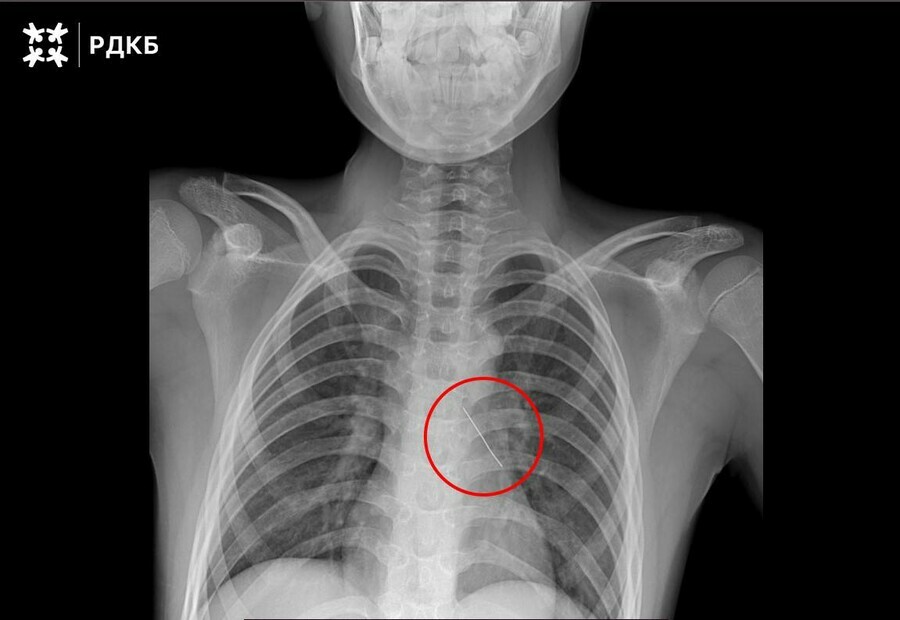

При поступлении в РДКБ он мог говорить только шепотом и испытывал сильные боли в груди. Рентген помог установить, что булавка оказалась в области нижней доли левого бронха. Изогнутая булавка пронзила бронх, что могло привести к серьезным нарушениям дыхания и даже коллапсу легкого.

«Специалисты отделения под визуальным контролем аккуратно извлекли инородное тело за колпачок булавки с помощью оптических щипцов. Это позволило минимизировать кровотечение, которое купировалось самостоятельно», — рассказали в Telegram-канале клиники.